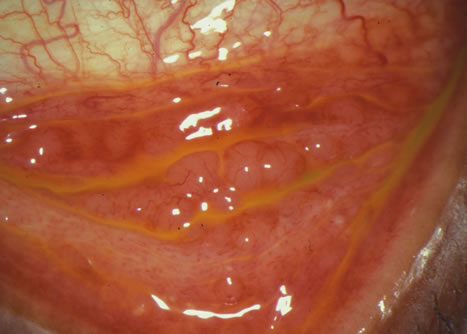

In the World Health Organization (WHO) grading system for acute trachoma, grade TF (trachoma follicles) represents mild trachoma with the presence of five or more follicles in the upper tarsal conjunctiva of at least 0.5 mm diameter (Fig. 11). Grade TI (trachoma inflammation) describes a more severe trachoma with pronounced inflammatory thickening of the upper tarsal conjunctiva that obscures more than half of the normal deep vessels (Fig. 12). Repeated infections cause scarring trachoma (grade TS) in which the upper eyelid is shortened and distorted causing entropion and trichiasis (grade TT), which abrades the eye. Blindness results from progressive corneal opacification (grade CO), which is related to the degree of entropion or trichiasis (Fig. 13).

Fig. 12. Trachomatous inflammation (grade TI). Follicles are seen on the palpebral conjunctiva associated with the presence of scarring. (Courtesy of Jose Gomes, MD.)